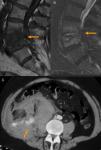

Procedimientos terapéuticosRizolisisCuando la infiltración facetaria produce un alivio sintomático consistente, aunque temporal, se puede plantear la rizolisis o denervación facetaria (fig. 4A). Este procedimiento trata de destruir las raíces sensitivas que inervan las facetas con el objeto de conseguir un alivio sintomático permanente. Estas raíces proceden de las ramas mediales del ramo dorsal del nervio espinal superior e inferior a cada articulación, por lo que se debe actuar en los 2 niveles para denervar una articulación facetaria.

A) Rizolisis. Colocación de la aguja en la base de la apófisis transversa donde pasa el ramo dorsal del nervio espinal. B) Ablación termal con radiofrecuencia del disco L5-S1. C) Reconstrucción multiplanar coronal de osteoma osteoide del arco vertebral (flecha). D) Imagen axial durante la ablación tumoral con radiofrecuencia. E) Vertebroplastia en un paciente con espondilitis anquilosante. F) Drenaje de absceso prevertebral tuberculoso. G) Drenaje de absceso brucelósico en compartimento del psoas.

Se puede conseguir mediante la inyección de etanol al 95% o mediante radiofrecuencia, continua o pulsada. Con el paciente en decúbito prono se coloca la punta del electrodo en el borde superior de la parte medial de la apófisis transversa. Si se usa radiofrecuencia continua, temperaturas superiores a 60°C durante 90seg son suficientes. Con radiofrecuencia pulsada la temperatura es inferior, en torno a 40°C. Los riesgos son menores, aunque su eficacia a largo plazo es inferior que con la radiofrecuencia continua30.

La ablación con radiofrecuencia (fig. 4B) también puede aplicarse a los ganglios nerviosos a nivel del foramen, al ganglio estrellado a nivel cervical, a la cadena simpática torácica en vecindad al cuello de las costillas, o a la cadena simpática lumbar, anterolateral a los cuerpos vertebrales L1-L5. Sus indicaciones incluyen la radiculitis, lesiones periféricas nerviosas secundarias a vasculitis, diabetes, amputación, y el dolor grave en pacientes oncológicos7.

Vertebroplastia y cifoplastiaLa vertebroplastia (fig. 4C) y la cifoplastia son técnicas ampliamente utilizadas en el tratamiento de las fracturas osteoporóticas y, en menor medida, en fracturas o lesiones vertebrales de causa tumoral. La principal diferencia técnica entre ambas es que la vertebroplastia introduce directamente el cemento en el hueso trabecular de la vértebra, mientras que la cifoplastia crea previamente 2 cavidades donde se deposita el cemento a baja presión. Tienen el objetivo común de aliviar la clínica dolorosa, pero la cifoplastia también trata de recuperar la altura vertebral.

Estudios recientes informan de una media de restauración de la altura vertebral de 4mm en la columna anterior y media del cuerpo vertebral con la cifoplastia. Sin embargo, el impacto clínico de esta recuperación de la altura es desconocido. Por otro lado, en algunos estudios clínicos de fracturas osteoporóticas no se encontraron diferencias estadísticamente significativas en la restauración de altura entre ambas técnicas35,36.

Dos ensayos clínicos ciegos aleatorizados recientes37,38, valorados por el editor como la mejor evidencia científica sobre la utilidad de la vertebroplastia39, concluyeron que el beneficio de esta no era mayor que el del procedimiento placebo, que solo inyectaba anestesia local en el área de la fractura. Sin embargo, los resultados de estos trabajos han sido ampliamente cuestionados en la literatura médica40,41, en aspectos como la selección de pacientes, la falta de seguimiento, el cambio de grupo, aspectos técnicos de la vertebroplastia, etc.

La proporción de complicaciones de la vertebroplastia y la cifoplastia es pequeña. Tampoco está demostrado que incremente el riesgo de nuevas fracturas frente al tratamiento conservador42. Las complicaciones específicas de esta técnica son la fuga de cemento al canal espinal, que puede provocar lesiones nerviosas, y las fugas venosas, con riesgo de tromboembolia pulmonar40.

Ablación tumoralLos tratamientos percutáneos de lesiones tumorales de la columna pueden tener una intención paliativa, cuando el objetivo es el alivio sintomático, o curativa, cuando el objetivo es la destrucción completa del tumor (fig. 4D y E).

La ablación puede ser termal (láser, radiofrecuencia, crioablación), o química (inyección de etanol).

Un ejemplo de ablación termal curativa es el uso de la radiofrecuencia en el tratamiento del osteoma osteoide43. En las metástasis espinales localizadas la ablación tumoral puede reducir el dolor de una forma más rápida que la radioterapia. La combinación con vertebroplastia trata de conseguir la estabilización mecánica del hueso. La necrosis coagulativa de la ablación termal puede favorecer una distribución más homogénea del cemento, mientras que el efecto exotérmico de este puede potenciar la acción antitumoral de la ablación44.

La ablación química mediante la inyección de etanol está indicada en los tumores osteolíticos, teniendo también un efecto analgésico secundario a la neurolisis. El contraste yodado se necesita para observar la distribución del alcohol, que no siempre es predecible, existiendo riesgo de fugas con lesión de estructuras neurológicas45.

Drenaje de abscesosEl drenaje percutáneo de abscesos (fig. 4F y G) bajo control de TC se considera el procedimiento de elección frente a la cirugía abierta en el tratamiento de las colecciones secundarias a infecciones piogénicas y tuberculosas en la mayoría de las regiones del cuerpo, incluida la columna y las estructuras paravertebrales. La evacuación del contenido purulento, junto al tratamiento antibiótico, acelera generalmente la mejoría clínica de los pacientes. El porcentaje de éxito suele ser superior en las infecciones piogénicas. En los abscesos tuberculosos crónicos las colecciones pueden presentar cápsulas fibrosas que no se colapsan perpetuando el acúmulo líquido y, por tanto, haciendo necesario el desbridamiento quirúrgico46.